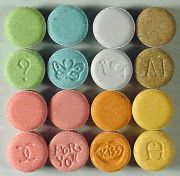

| 2021年7月26日 (一) 18:22 | Ecstasy monogram.jpg (文件) |  |

100 KB | 77921020 | Uploaded with SimpleBatchUpload | 1 |